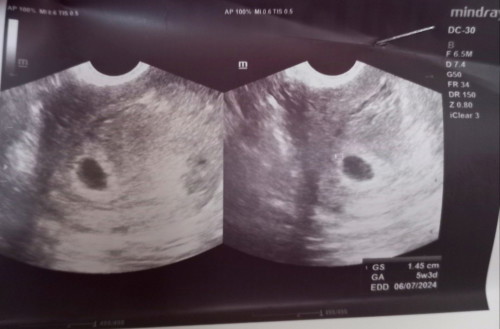

CS: 5weeks & 3 days Preggy

Mommies, sino po may same case sakin dito? Ayun sa TVS result ko 5weeks & 3 days pregnant po ako, pero gestational sac lang po nakita wala pa pong embryo. Pinanghinaan na po ako nang malaman ko na wala pang yolk sac na nakita, sabi ni doc mag antay pa ako ng 2-3weeks baka meron pa ma develop. Kasi possible din po daw na Blighted ovum. Baka may same case po dito. ðŸ˜ðŸ˜#pleasehelp #bantusharing